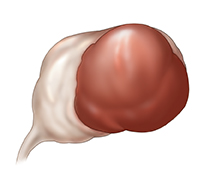

Endometrioma

En ocasiones, crece un tejido similar al recubrimiento del útero (endometrio) y se convierte en parte del ovario. Este tipo de quiste se suele llamar quiste de "chocolate" porque es de color marrón oscuro. Estos quistes pueden crecer en uno o en ambos ovarios y suelen causar dolor, especialmente cerca del momento de la menstruación o durante el acto sexual.